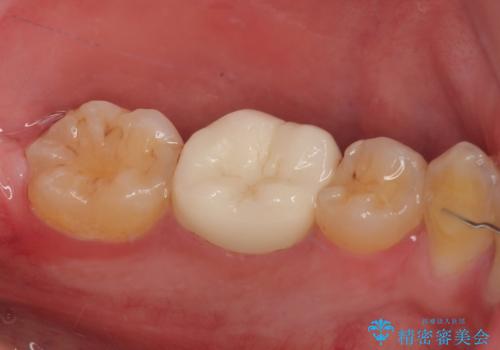

虫歯による不快な症状がなくなり喜んでいただきました。セラミックの被せものが入った後の違和感なく過ごせているそうです。矯正治療終了直後の被せもの治療なのでリテーナーの作成回数をできるだけ少なく迅速に行うことを考慮して治療を行いました。

今後、ホワイトニングを行う予定なので、患者様のご希望により、周りの歯に比べてあえて白い被せものを作成しました。